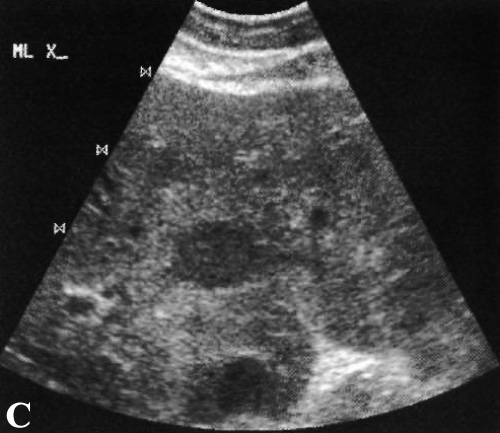

У беременных или у пациентов, принимающих эстрогенные препараты, гемангиомы могут увеличиваться – гормонозависимые гемангиомы. Цветная допплерография демонстрирует либо полное отсутствие кровотока, либо он незначительный (фото 9).

Фото 9. Гемангиомы печени. А и В – характерная ультразвуковая картина: стрелками обозначено гиперэхогенное образование возле печеночной вены. Цветная допплерография демонстрирует отсутствие кровотока в образовании, что обусловлено очень медленным продвижением крови по этим образованиям. С – стрелками обозначена гемангиома, ультразвуковая картина которой имитирует гепатоцеллюлярный рак: крупное неоднородное образование локализовано в заднем сегменте правой доли печени. Компьютерная томография подтвердила диагноз гигантской гемангиомы

Ультразвуковая картина гемангиомы печени демонстрирует хорошо очерченные гиперэхогенные образования округлой или овальной формы. Гиперэхогенная структура образования обусловлена наличием множественных поверхностей соприкосновения стенки синуса и наличия крови. Может наблюдаться акустический эффект усиления. Гемангиомы больших размеров могут визуализироваться как сложные образования с гипоэхогенными участками некроза, фиброза, кровоизлияния или тромбоза – эта картина напоминает метастазы из ЖКТ, гепатоцеллюлярный рак, очаговую узелковую гиперплазию и аденомы.